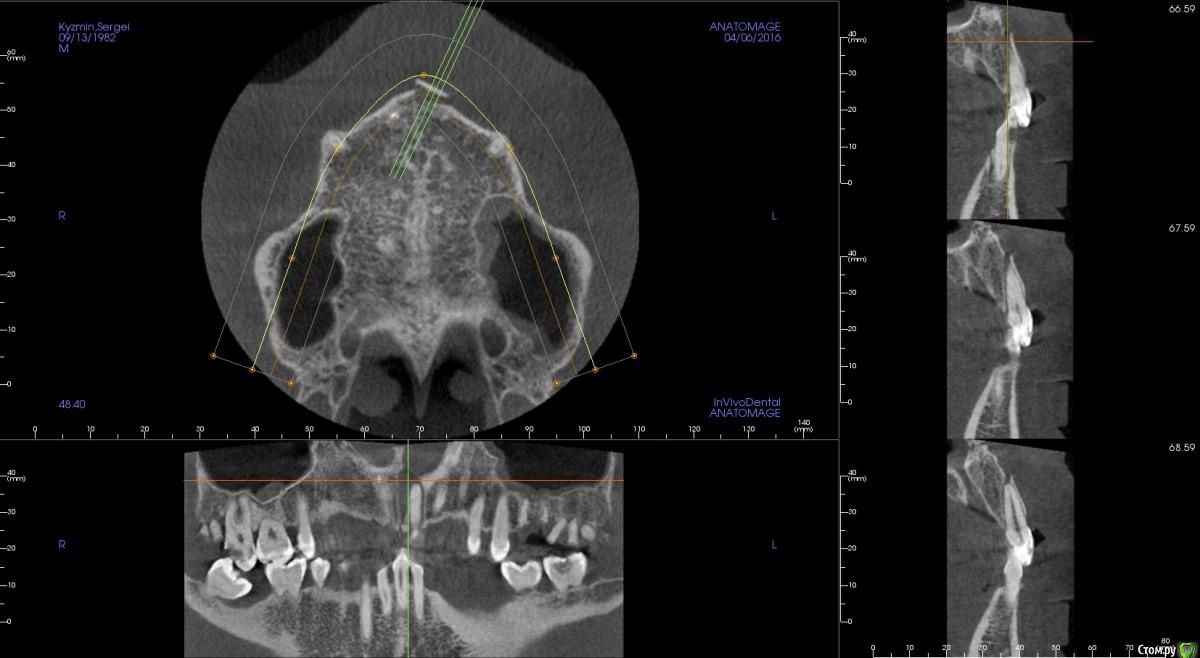

kamranchick Опубликовано 17 апреля, 2016 Поделиться Опубликовано 17 апреля, 2016 Пришел пациентДок привет, что то зуб шатается, можно ли его оставить, вот такие дела)как бы вы поступили бы? Ссылка на комментарий